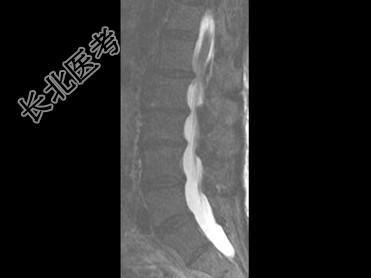

- 单项选择题男,59岁, 硬膜外麻醉后背痛1周余,结合MRI检查, 最可能的诊断是 ( )

E、硬膜外血肿